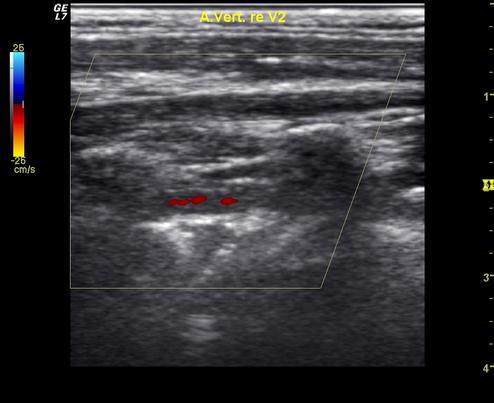

Ultraschallaufnahme einer Dissektion der Arteria vertebralis im Halsbereich

Dissektionen der Halsarterien entstehen meist ohne eine relevante mechanische Ausseneinwirkung!

Die Diagnose einer Dissektion ist bisweilen schwierig. Eine sorgfältige Untersuchung, Ultraschalluntersuchungen der Halsschlagadern und Kernspintomographien oder Computertomographien können eine Dissektion beweisen.